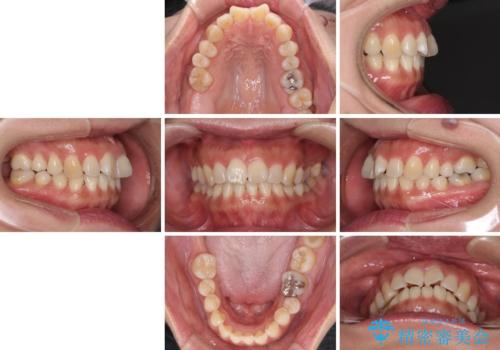

- 上下前歯の叢生を気にして来院された患者様です。

費用を抑え、期間もあまりかけずに治療をしたいとのことで、インビザライン・ライトを用いて矯正治療を行うこととしました。

インビザライン・ライトは、製作できるアライナーの枚数に制限があるため、移動可能な量に限りがあります。

一方で、半年から1年程度で治療を終えることができるため、軽度の歯列不正の患者様には大変お勧めです。